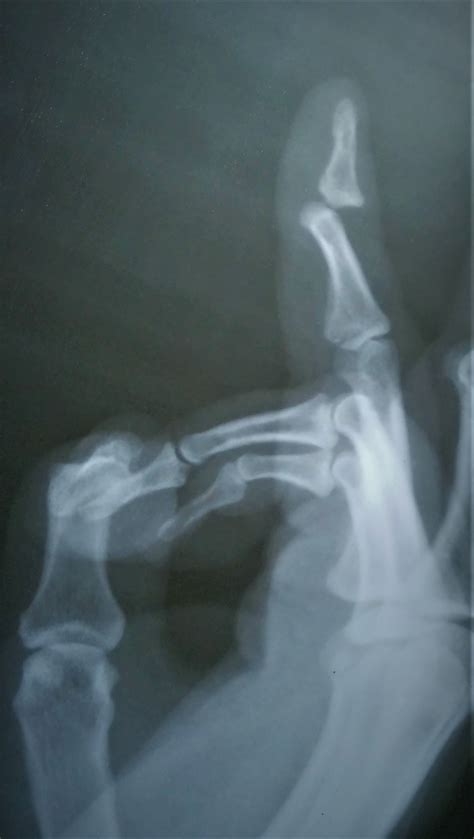

• Deformity: The finger may appear bent or misshapen.

Diagnosing a dislocated pinky finger typically involves a physical examination and imaging tests. The doctor will:

• Examine the finger to assess the extent of the injury.

• Order X-rays to confirm the dislocation and rule out any fractures.

In some cases, additional imaging tests like an MRI or CT scan may be required to get a more detailed view of the injury.

• dislocated pinky finger xray